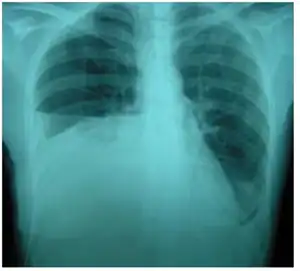

O urinotórax é definido como o encontro de urina na cavidade pleural que circunda os pulmões. Geralmente é causada por uropatia obstrutiva. É diagnosticado principalmente pela análise do líquido pleural. O tratamento envolve o tratamento da condição subjacente, que normalmente resulta na resolução do urinotórax. É uma causa extremamente rara de derrame pleural.

O urinotórax é causado pelo encontro de urina na cavidade pleural que circunda os pulmões.[1] As características das pessoas afetadas pelo urinotórax são mal definidas. Sintomas urológicos tendem a ocorrer, enquanto sintomas respiratórios são geralmente inexistentes ou leves.[2] Dificuldade respiratória, ocorrendo em moderados a grandes derrames pleurais, é o sintoma respiratório mais comum.[3] Outros sintomas incluem febre, dor abdominal, dor torácica e urinação reduzida.[2] Geralmente ocorre poucas horas após a condição causadora.[4]

Como os principais sintomas são geralmente urológicos em vez de respiratórios, a condição requer a exclusão de outras condições e a identificação de sintomas específicos antes do diagnóstico.[7] A análise do fluido pleural é uma forma de diagnosticar a condição. O líquido pleural é geralmente cor de palha e tem um cheiro distinto, como amônia. O fluido geralmente tem uma quantidade de células nucleadas de 50 a 1500 por cm3.[3] O pH do fluido é geralmente entre 5 e 7.[9] Os fatores primários para o diagnóstico de urinotórax pelo líquido pleural incluem baixo teor de proteína e alto teor de lactato desidrogenase.[10] Níveis baixos de glicose e acidez também são descritos, mas não são formas confiáveis de diagnosticar ou descartar o urinotórax.[6] O fator de diagnóstico químico mais importante do fluido é que a proporção de creatinina para soro é superior a 1 e geralmente superior a 10.[10]